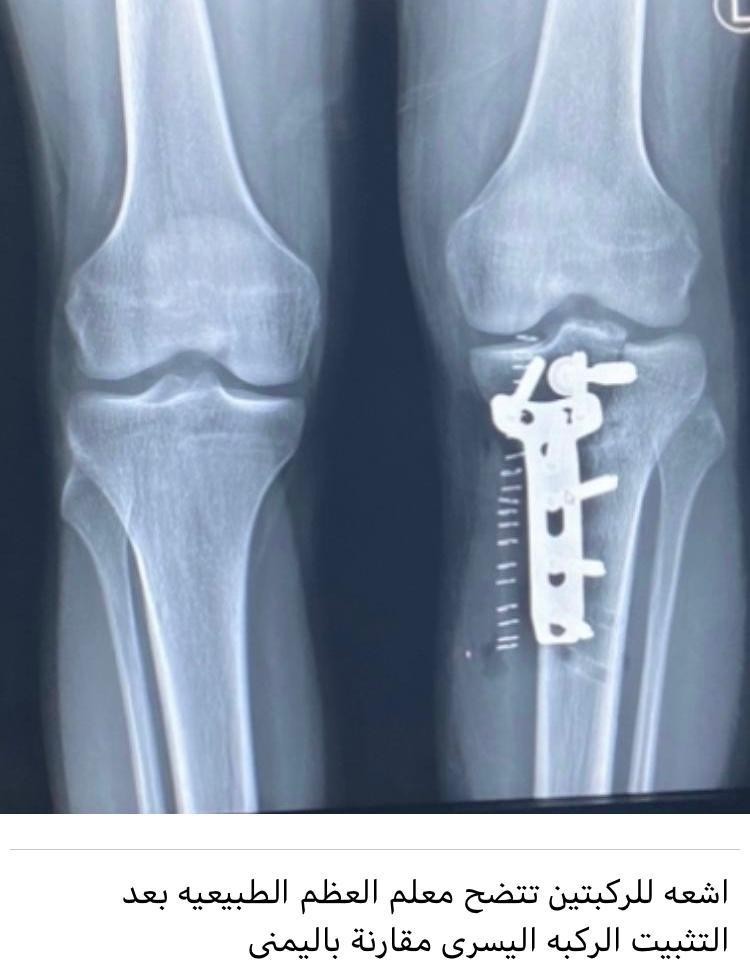

تمكن فريق طبي بمستشفى أبها الخاص  العالمي برئاسة استشاري جراحة العظام  الدكتور محمد لافي العتيبي من  إعادة مفصل الركبة لوضعه الطبيعي لعشريني تعرض لحادث سير  بسبب دراجة نارية نتج عنه كسور معروفة بخطورتها على الأعصاب والأوردة ,  والشرايين الموجودة  خلف مفصل الركبة، وقد  تم خلال العملية  تثبيت كسور كانت  تستدعي تدخلاً طارئاً  لضمان  عدم البتر  لاسمح الله وعلى الرغم من وجود خطورة لوجود الأوردة والأعصاب، والشرايين والتي  تطلبت العملية المزيد من الحرص والدقة أثناء إجراء العملية.

وفي التفاصيل أشار العتيبي إلى  أن الكسور داخل المفاصل تعتبر  بشكل عام ذات خطورة عالية وتزداد  خطورةَ إذا ما حدثت في المفاصل الكبيرة مثل الركبة حيث يكون التدخل الجراحي حتمياَ لرد تكوين المفصل العظمي بشكل كامل لتلافي الإعاقة ,  وأضاف أنه عندما يحدث الكسر  بشكل كامل خلف الركبة مباشرهً فانه يكون في غاية الخطورة من اللحظة الأولى وذلك لمرور جميع الأعصاب والشرايين والأوردة خلف الركبة ملاصقة للعظم  في حدود مليميترات بسيطة والتي في حال لا سمح الله أصابها قطع أو ضغط من كسور الجدار الخلفي للركبة فإن ذلك يستدعي حلاً طارئاً جداَ لضمان بقاء الطرف السفلي سليماً , ولكي يتم تجنب  الإعاقة الشديدة التي قد تصل للبتر .

وذكر أن هذه الحالة لشاب في العشرين تعرض لحادث سير دراجة نارية , وهي من الحوادث التي تنتج عنها مثل هكذا كسور ولحسن الحظ لم تؤثر الكسور على الاعصاب، والأوردة والشرايين، إلا أنها أخلت بثبات المفصل، وهشمت الغضروف وأصبح التدخل الجراحي حتمياً لرد الكسر، واستعادة قوام المفصل بشكل سريع قبل التئام المفصل بشكل معيق أو تحرك الكسور نحو الخلف حيث منطقة الشريان الرئيس للرجل مؤكداً بأنه قد تم إجراء العملية  لتثبيت الكسور بشكل دقيق رغم خطورة التدخل الجراحي، وحتمية استخدام القطع الجراحي خلف المفصل مباشرة للتعامل الأمثل مع الكسر، وتثبيته بشكل يضمن سلامة المفصل لهذا الشاب ، وتمت العملية بنجاح بحمد الله وتوفيقه.